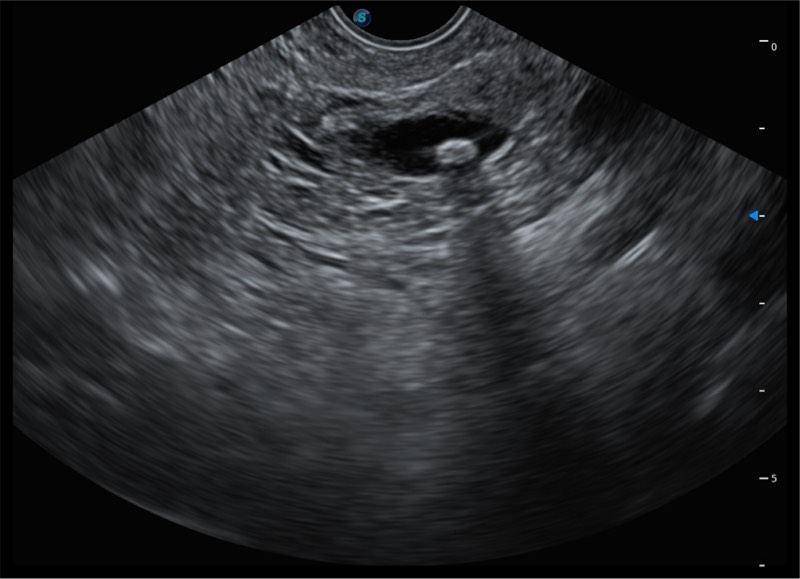

基于二十年的超声技术积累,亚星官网提供了最新一代的独立超声主机,在提供高质量图像的同时满足多学科使用。具备常见多普勒技术并提供弹性成像、声学造影等高端影像技术。新一代传感器具有更强的抗干扰能力并减少图像伪影。

150°超声扫描角度

4-12MHZ宽频输出